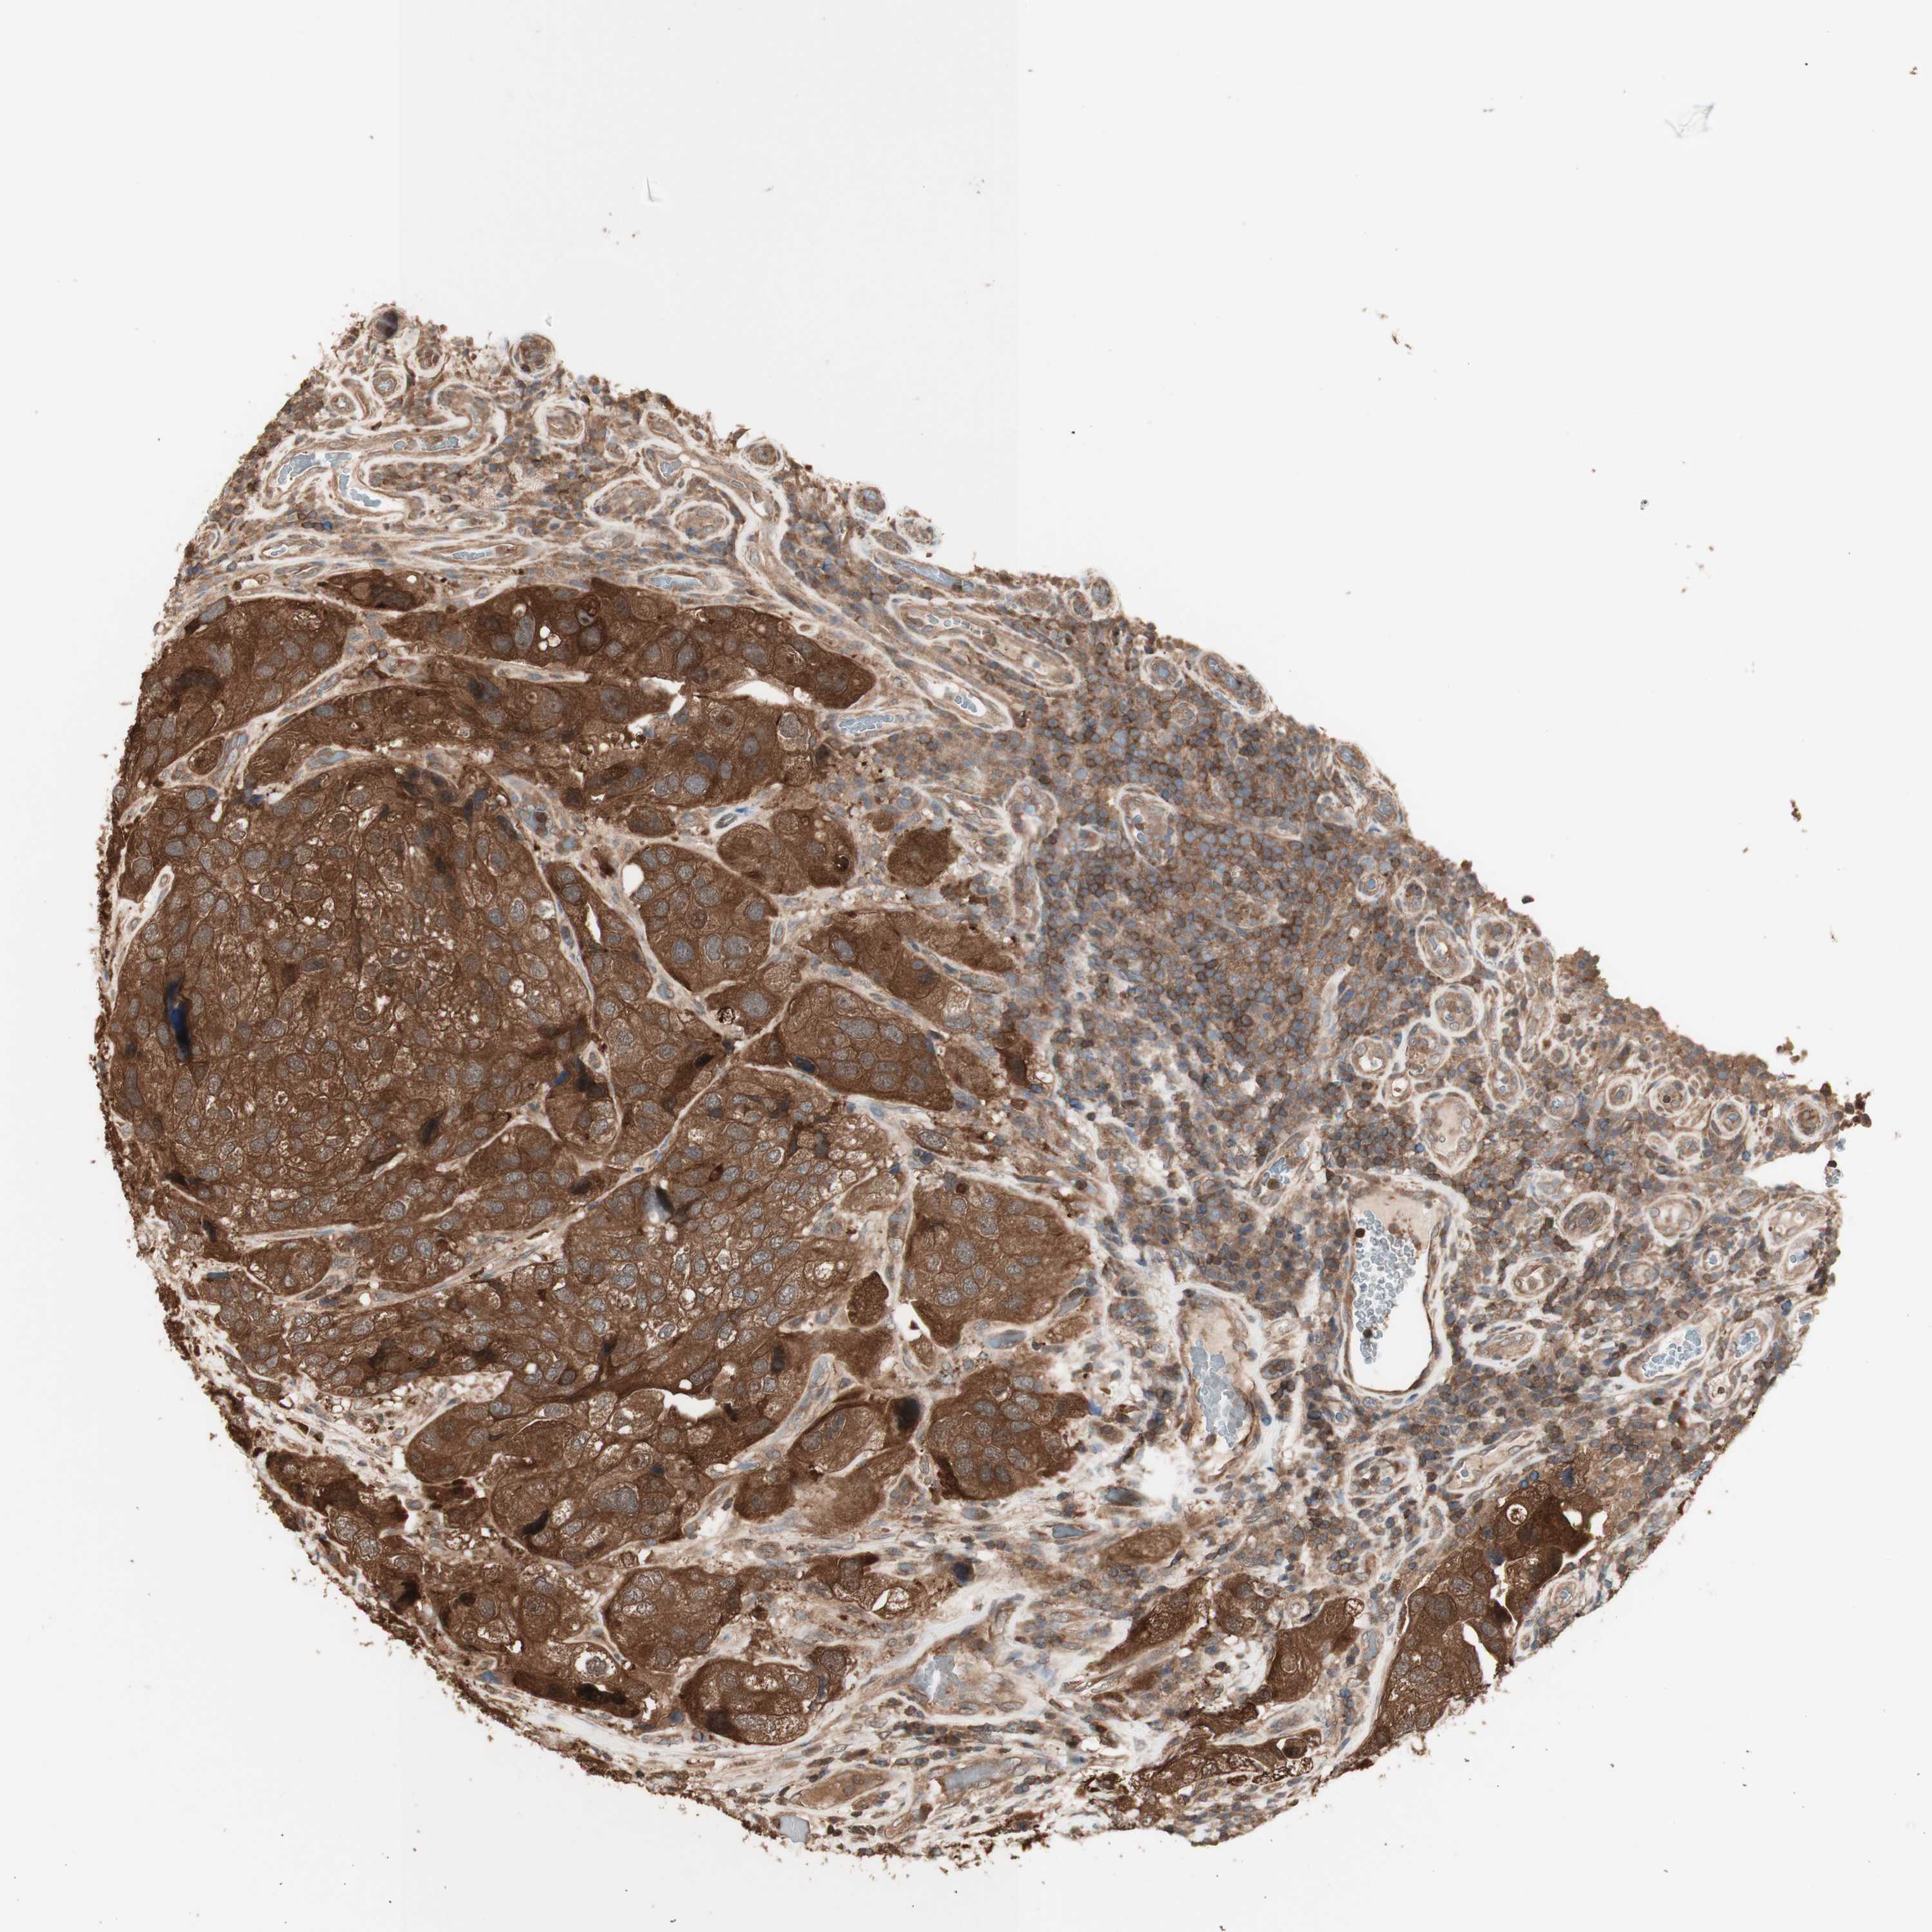

UROTHELIAL CANCER - Protein expressioni

A mouse-over function shows sample information and annotation data. Click on an image to view it in a full screen mode. Samples can be filtered based on level of antibody staining by selecting one or several of the following categories: high, medium, low and not detected. The assay and annotation is described here.

Note that samples used for immunohistochemistry by the Human Protein Atlas do not correspond to samples in the TCGA dataset.

Antibody stainingi

Antibody staining in the annotated cell types in the current human tissue is reported as not detected, low, medium, or high, based on conventional immunohistochemistry profiling in selected tissues. This score is based on the combination of the staining intensity and fraction of stained cells.

Each image is clickable and will lead to virtual microscopy that enables deeper exploration of all samples and also displays staining intensity scores, fraction scores and subcellular localization as well as patient and tissue information for each sample.

Antibody HPA007925

Antibody HPA011212

Antibody CAB003759

Antibody CAB080290

Staining

High

Medium

Low

Not detected

Intensity

Strong

Moderate

Weak

Negative

Quantity

>75%

75%-25%

<25%

None

Location

Nuclear

Cytoplasmic/membranous

Cytoplasmic/membranous,nuclear

Urothelial carcinoma, Low grade

Urothelial carcinoma, High grade